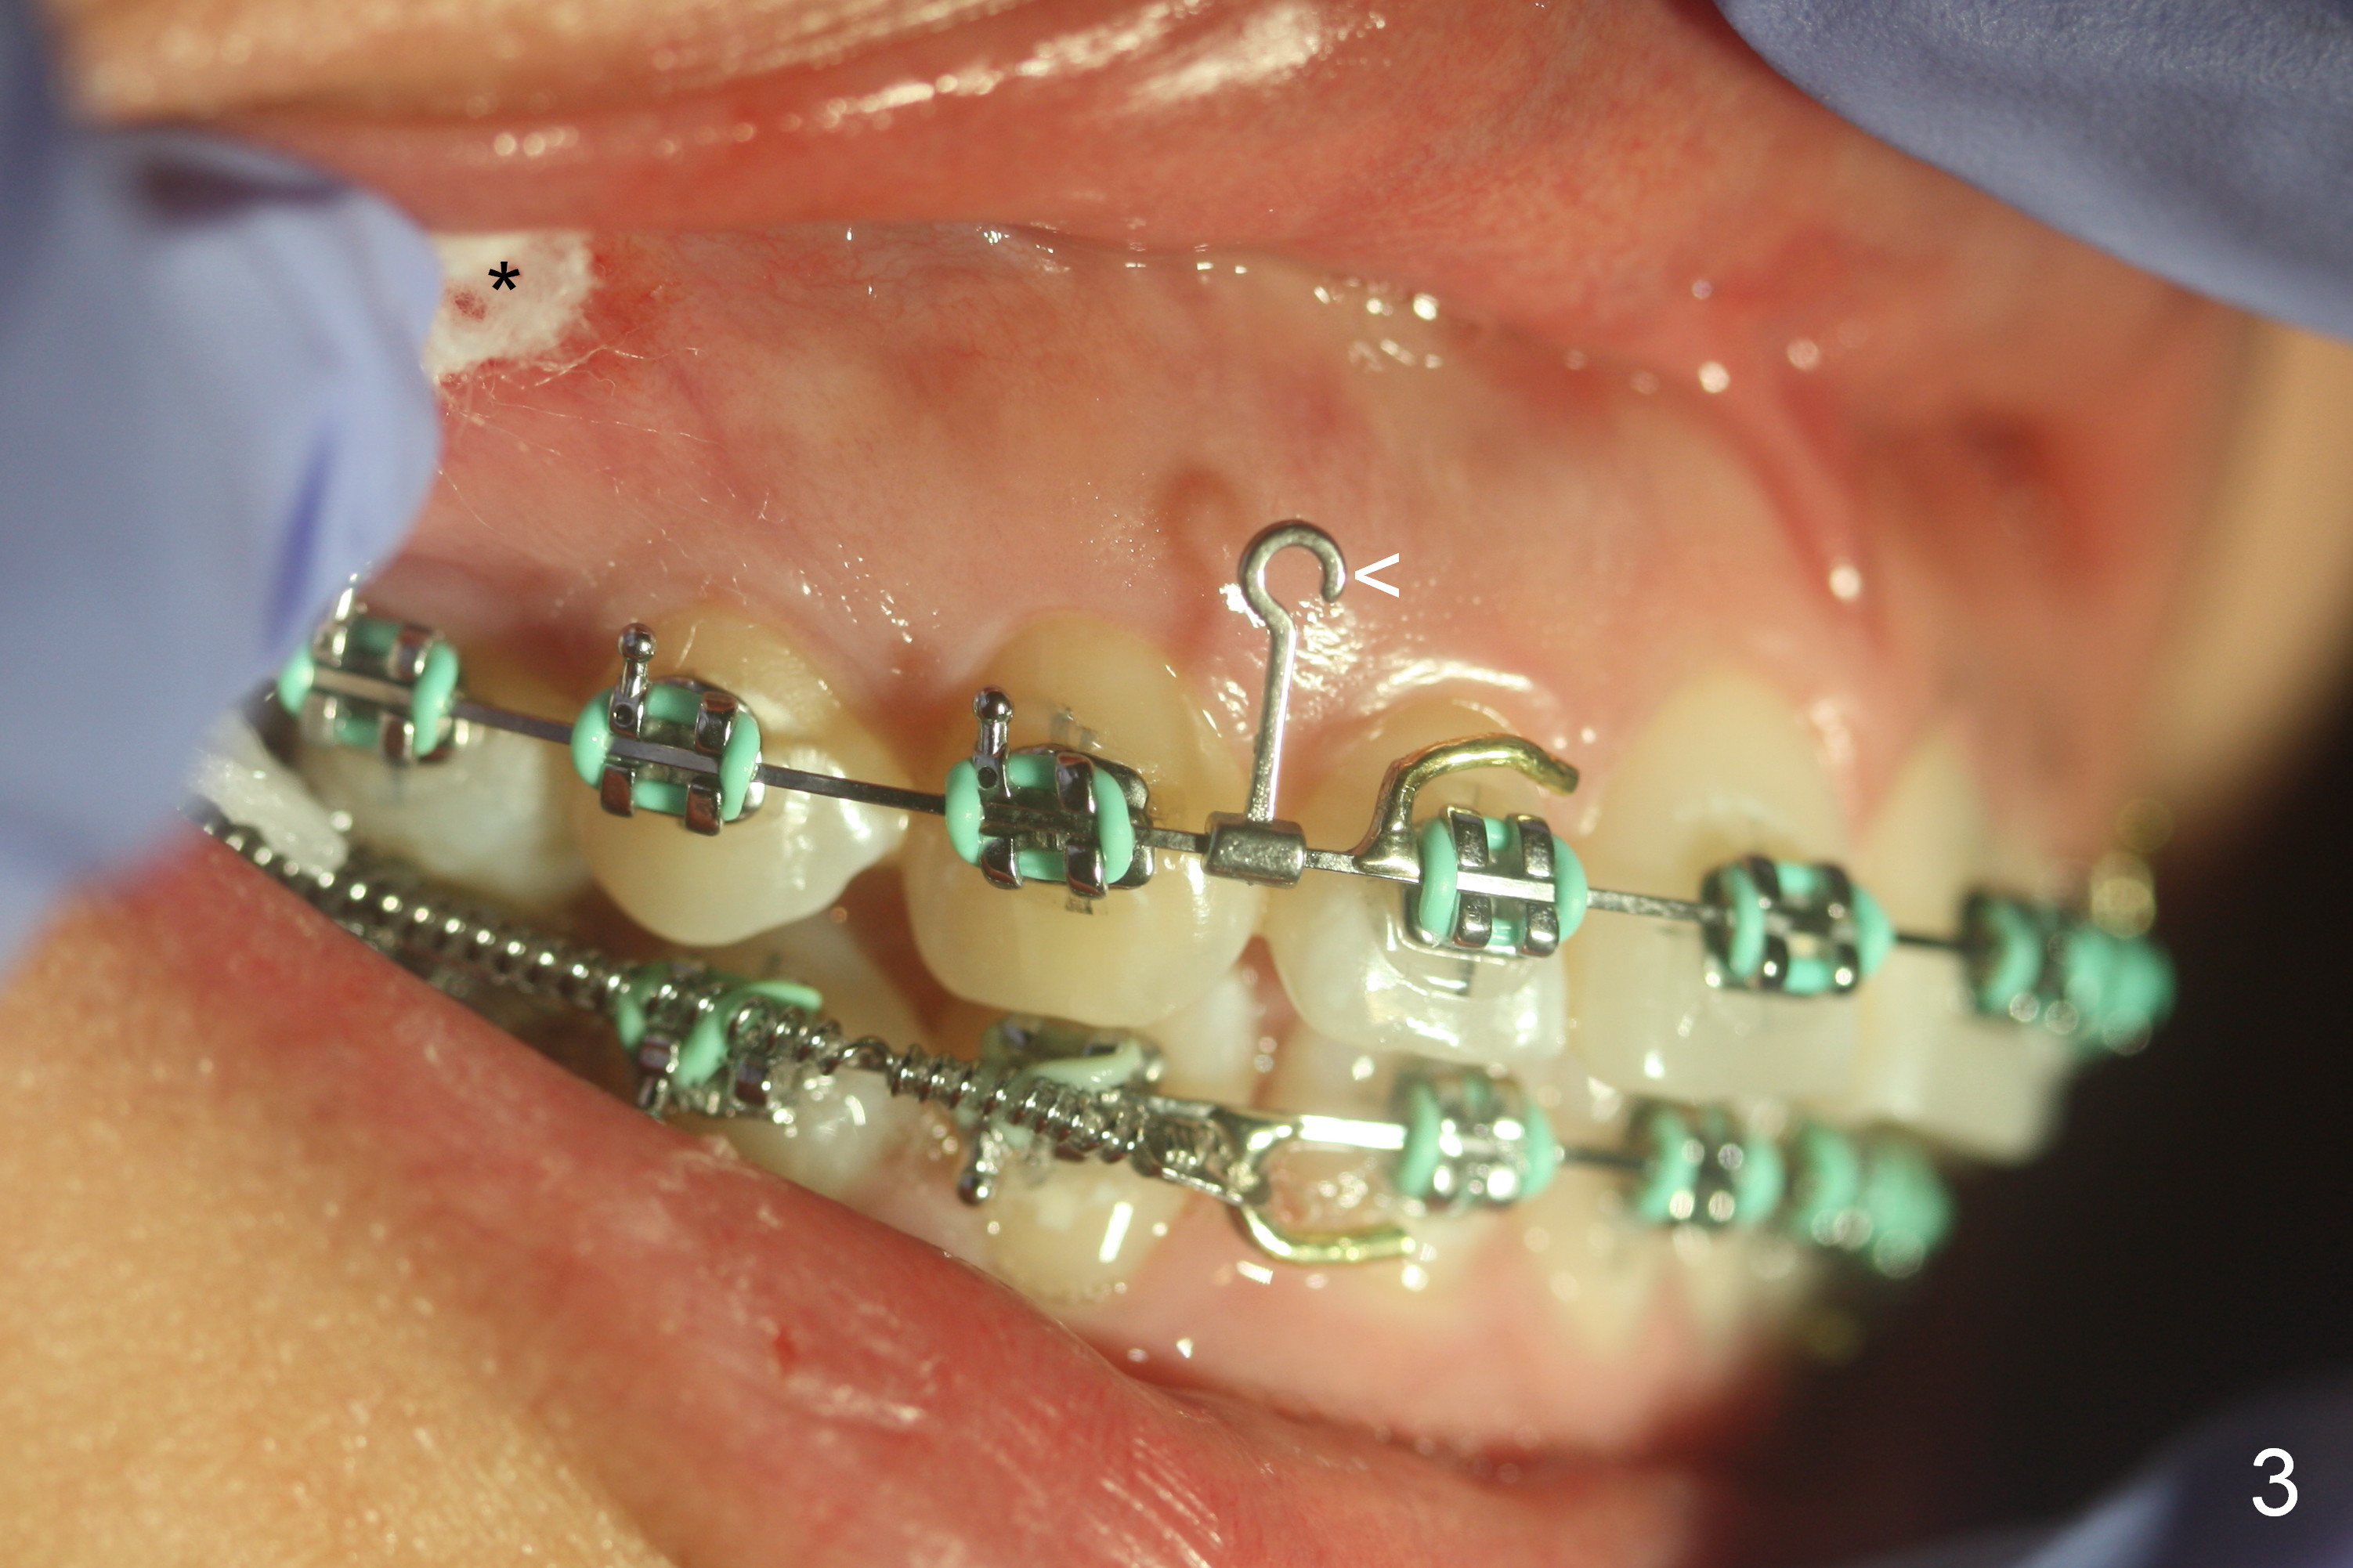

5. White Ortho box: closed coil springs, Crimpable Power Hooks (right and left, Fig.3 <), crimping forceps

6. Incision is made 4-5 mm above the mucogingival junction, over the maxillary 1st molar (Fig.3 *)

7. Rationale: the Zygomatic mini implant (Fig.4 *) will be placed higher than the existing one (<)